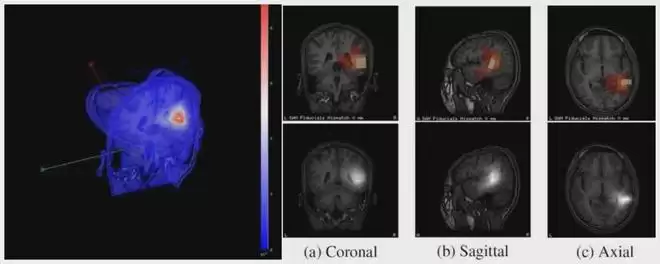

2010年5月至10月,杨寅飞参与了一项跨校、跨国合作研究,与南京航空航天大学的郑刚及田纳西理工大学的 Forrest Sheng Bao合作,围绕AI与脑磁图(MEG)结合的癫痫诊断软件展开研究,目标是验证机器学习方法在癫痫诊断中的可行性。

在具体实现上,他参与开发了一套用于MRI图像配准与可视化的软件系统,并结合基于SAM-kurtosis algorithm(SAM[g2])计算的结果,对来自CTF脑磁图系统的数据进行处理。该项目源码已开源,并发布在Source Forge平台。

▲MRI图像可视化系统CTF-SAM-OUT的图像演示(图源:Source Forge)